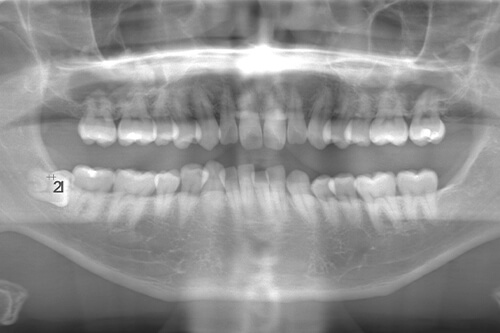

CASE 2

| 年齢・性別 | 30代・男性 |

|---|---|

| 主訴 | 左上下親知らず抜きたい |

| 抜歯期間 | 30分 |

| 抜歯費用 | 約2,500円(保険内) 別途CT撮影で3,000円 |

| 抜歯内容 | 左上下の親知らず抜歯 |